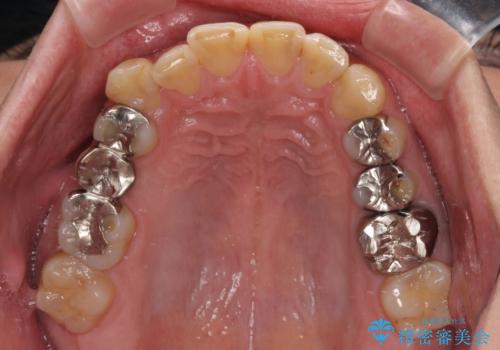

- 近医にて下顎奥歯の抜歯が必要と言われたとのことで来院された患者様です。

診察の結果、奥歯は左右ともに抜歯が必要な状態でした。

他の銀歯も気になっており、セラミックにしたいとの要望があり、詳しくお話をすると、デコボコの歯ならびも整えたいとのことでした。

抜歯が必要な歯は事前に抜歯をし、その後ワイヤー装置にて歯列矯正を行い、途中でインプラントを埋入し、オールセラミッククラウンにて補綴治療を行うこととしました。